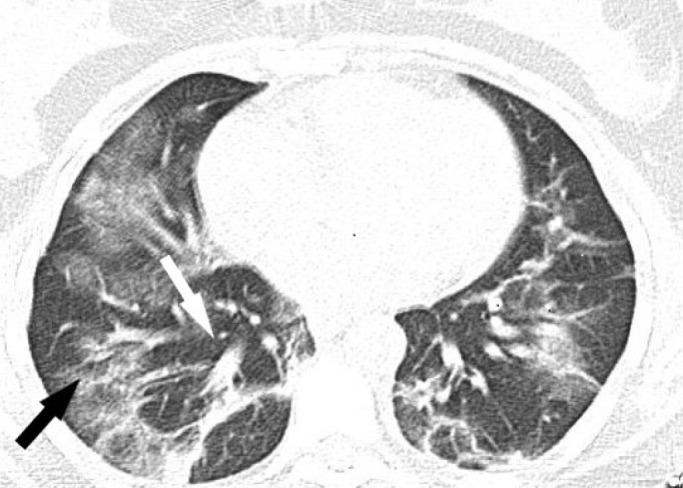

Numerous neurological manifestations associated with COVID-19 have been reported. However, abducens nerve palsy (ANP) associated with COVID-19 is very rare and mostly related to accompanying respiratory symptoms. Here we present a 29-year-old woman with unilateral ANP manifesting with diplopia and positive SARS-CoV-2 S antibodies, which were checked later. On admission, she had signs of viral pneumonia in thorax CT without any respiratory symptoms. Her cranial neuroimaging revealed no abnormality. Following treatment with favipiravir 2x1600 mg loading dose and then 2x600mg daily maintenance, dexamethasone 8 mg/day and enoxaparin 6000 IU/day, her CT findings recovered completely whereas her ANP only partially resolved. One week after the end of COVID-19 treatment, she also developed Herpes simplex keratitis which was successfully treated with valacyclovir. It should be kept in mind that isolated abducens nerve palsy may be the only finding of COVID-19 cases without any respiratory symptoms.

已有许多与新冠病毒病(COVID-19)相关的神经学表现的报道。然而,与COVID-19相关的外展神经麻痹(ANP)非常罕见,且大多与伴随的呼吸道症状有关。在此,我们报告一名29岁女性,出现单侧ANP,表现为复视,后来检测出严重急性呼吸综合征冠状病毒2(SARS-CoV-2)S抗体呈阳性。入院时,她胸部CT有病毒性肺炎迹象,但无任何呼吸道症状。她的头颅神经影像学检查未发现异常。在用法匹拉韦2×1600mg负荷剂量,然后每日2×600mg维持剂量、地塞米松8mg/天和依诺肝素6000IU/天治疗后,她的CT表现完全恢复,而她的ANP仅部分缓解。COVID-19治疗结束一周后,她还患上了单纯疱疹性角膜炎,用伐昔洛韦成功治疗。应记住,孤立的外展神经麻痹可能是无任何呼吸道症状的COVID-19病例的唯一表现。